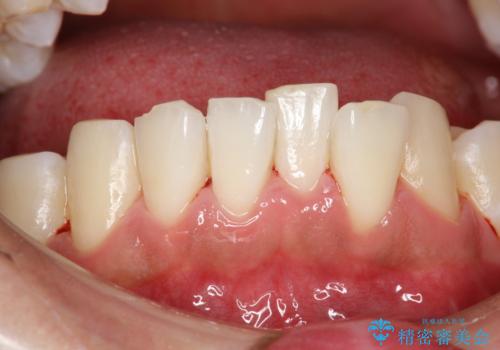

タバコのヤニを取って歯を白くしたい

- タバコを吸われる方で、ヤニを取って歯を白くしたいとのことでした。

歯の表面についた汚れがかなり頑固な汚れだったため、PMTC(エアフロー)の60分コースにて施術しました。

ヤニは歯につくと表面がざらざらしたような舌触りになります。

ざらざらしたところに歯石や茶渋の汚れプラークなどが付きやすいため

タバコを吸われる方は見た目が気にならない方でも歯周病や虫歯の予防としてクリーニングを行うことをお勧めします。